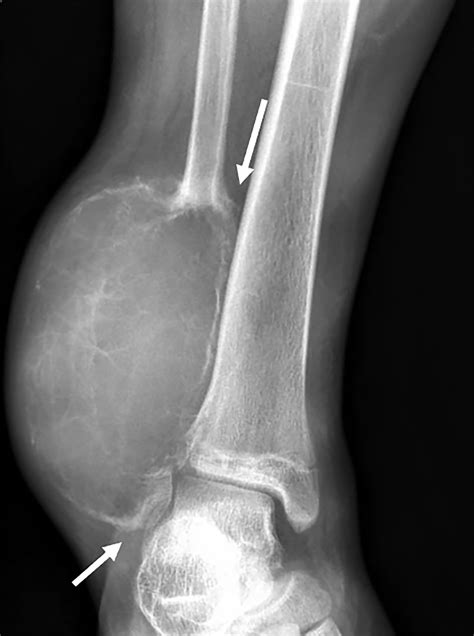

• Imaging Tests: Imaging tests, such as X-rays, CT scans, or MRI scans, can provide detailed images of the bone and surrounding tissues. These tests help identify the cause of the lump and determine its extent.

• Bone Tumors: These can be either benign (non-cancerous) or malignant (cancerous). Benign tumors, such as osteochondromas or enchondromas, are generally harmless but can cause discomfort or affect mobility. Malignant tumors, like osteosarcoma, are more serious and require immediate medical attention.

• : Bone cysts, such as aneurysmal bone cysts, can develop within the tibia and appear as lumps. These cysts are usually benign but can cause pain and weaken the bone.